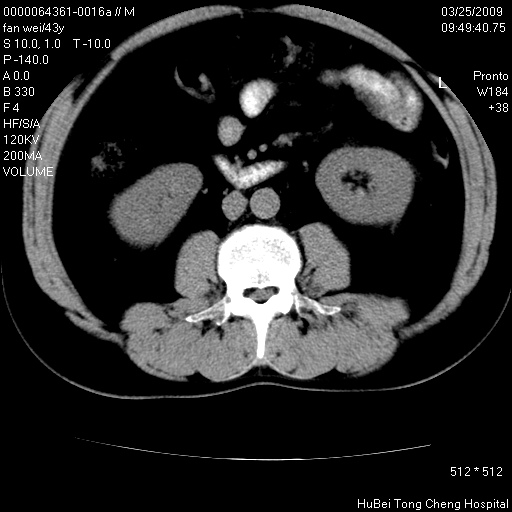

患者 男,43岁。左侧腰部不适两天。平素健康。无家族遗传病史。

腹部彩超提示:1)轻度脂肪肝。2)左肾多发囊性占位性病变;建议行进一步检查。

临床诊断:左肾多发囊性占位性病变,性质待定(多发肾囊肿?)。

双肾ct轴位平扫+增强扫描(层厚10mm,螺距1.0,重建间隔10mm),图像如下: